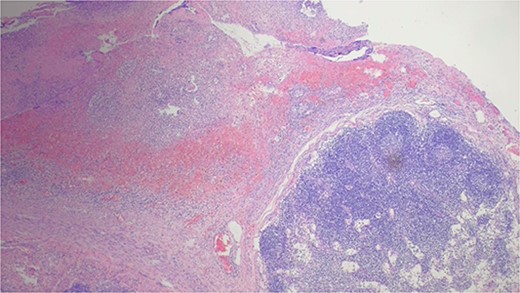

The patient commenced oral intake three days following the operation and was discharged seven days later. The postoperative pathology report indicated chronic diverticulitis with ectopic pancreatic mucosa and chronic appendicitis (Figs 3 and 4).

The pathology result of chronic diverticulitis with ectopic pancreatic mucosa.